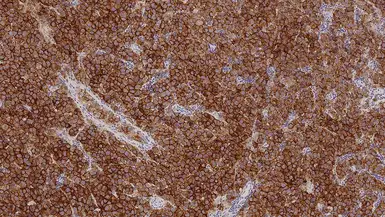

IHC-P analysis of human seminoma tissue using GTX01925 Placental Alkaline Phosphatase antibody [8A9]. Note the strong membrane and cytoplasmic staining of malignant cells.